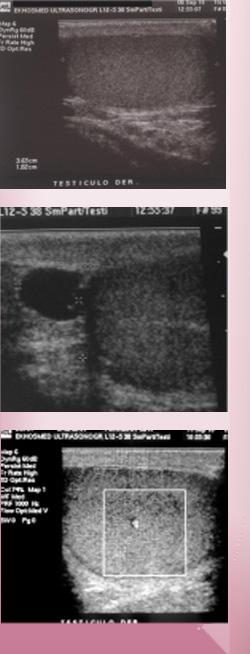

Estudia los testículos y

epidídimos además de

analizar el líquido que

los rodea.

Es la primera prueba

diagnóstica en pacientes

con dolor testicular,

aumento de volumen del

testículo, ectopia

testicular, inflamación,

masa palpable o trauma.